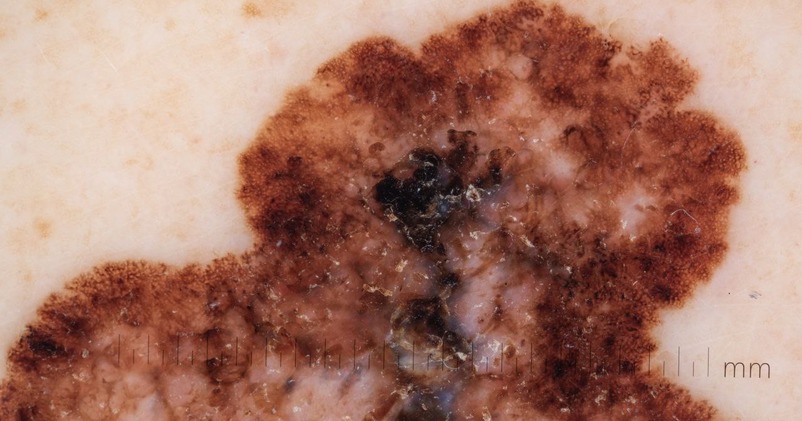

Paramount Skin Check offers professional, in-person skin assessments using advanced imaging technology to detect early signs of skin cancer and other skin conditions.

Each case is reviewed by a fully licensed consultant dermatologist, ensuring that your results are based on expert clinical judgment—not just algorithms.

we believe that early detection requires the eyes and experience of real specialists who understand the subtle warning signs that machines may miss. Within 48 hours,